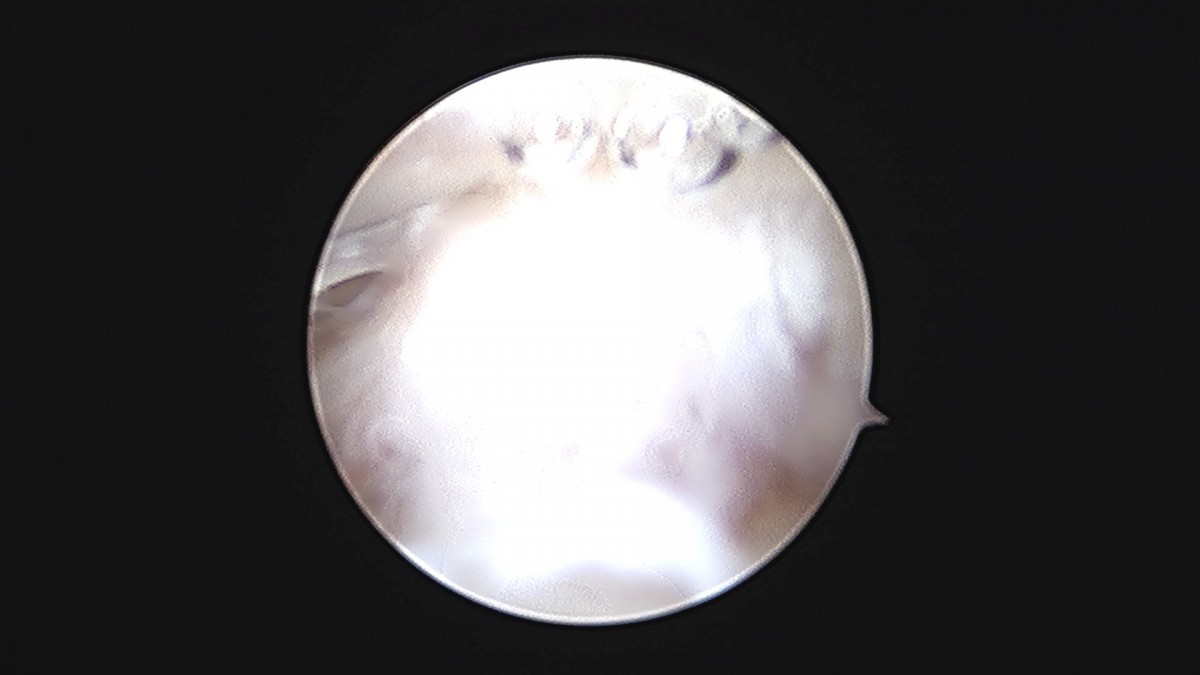

이재상원장님 발목 연골병변 제거술 및 골수 자극술 장경O 환자

dae765e4d9ac96aee867c9d6292d8784_1758006813_6676.jpg